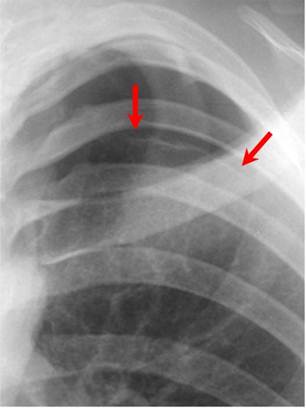

图2 白色胸膜线(红箭头),这是气胸的唯一最佳指征

治疗方法包括:简单抽吸(成功率> 50%)和胸腔穿刺术

(90%有效)。预后:同侧复发率30%,对侧复发率10%。